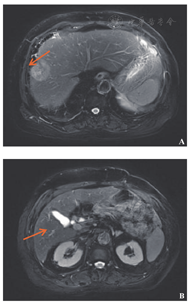

术后在外院行8个周期FOLFOX化疗(奥沙利铂85 mg/m2,ivgtt+氟尿嘧啶280 mg/m2,iv bolus+氟尿嘧啶1.4 g/m2,civ+亚叶酸钙280 mg/m2,ivgtt),2012年07月我院肝脏增强磁共振成像检查提示:肝多发转移瘤(图1)。